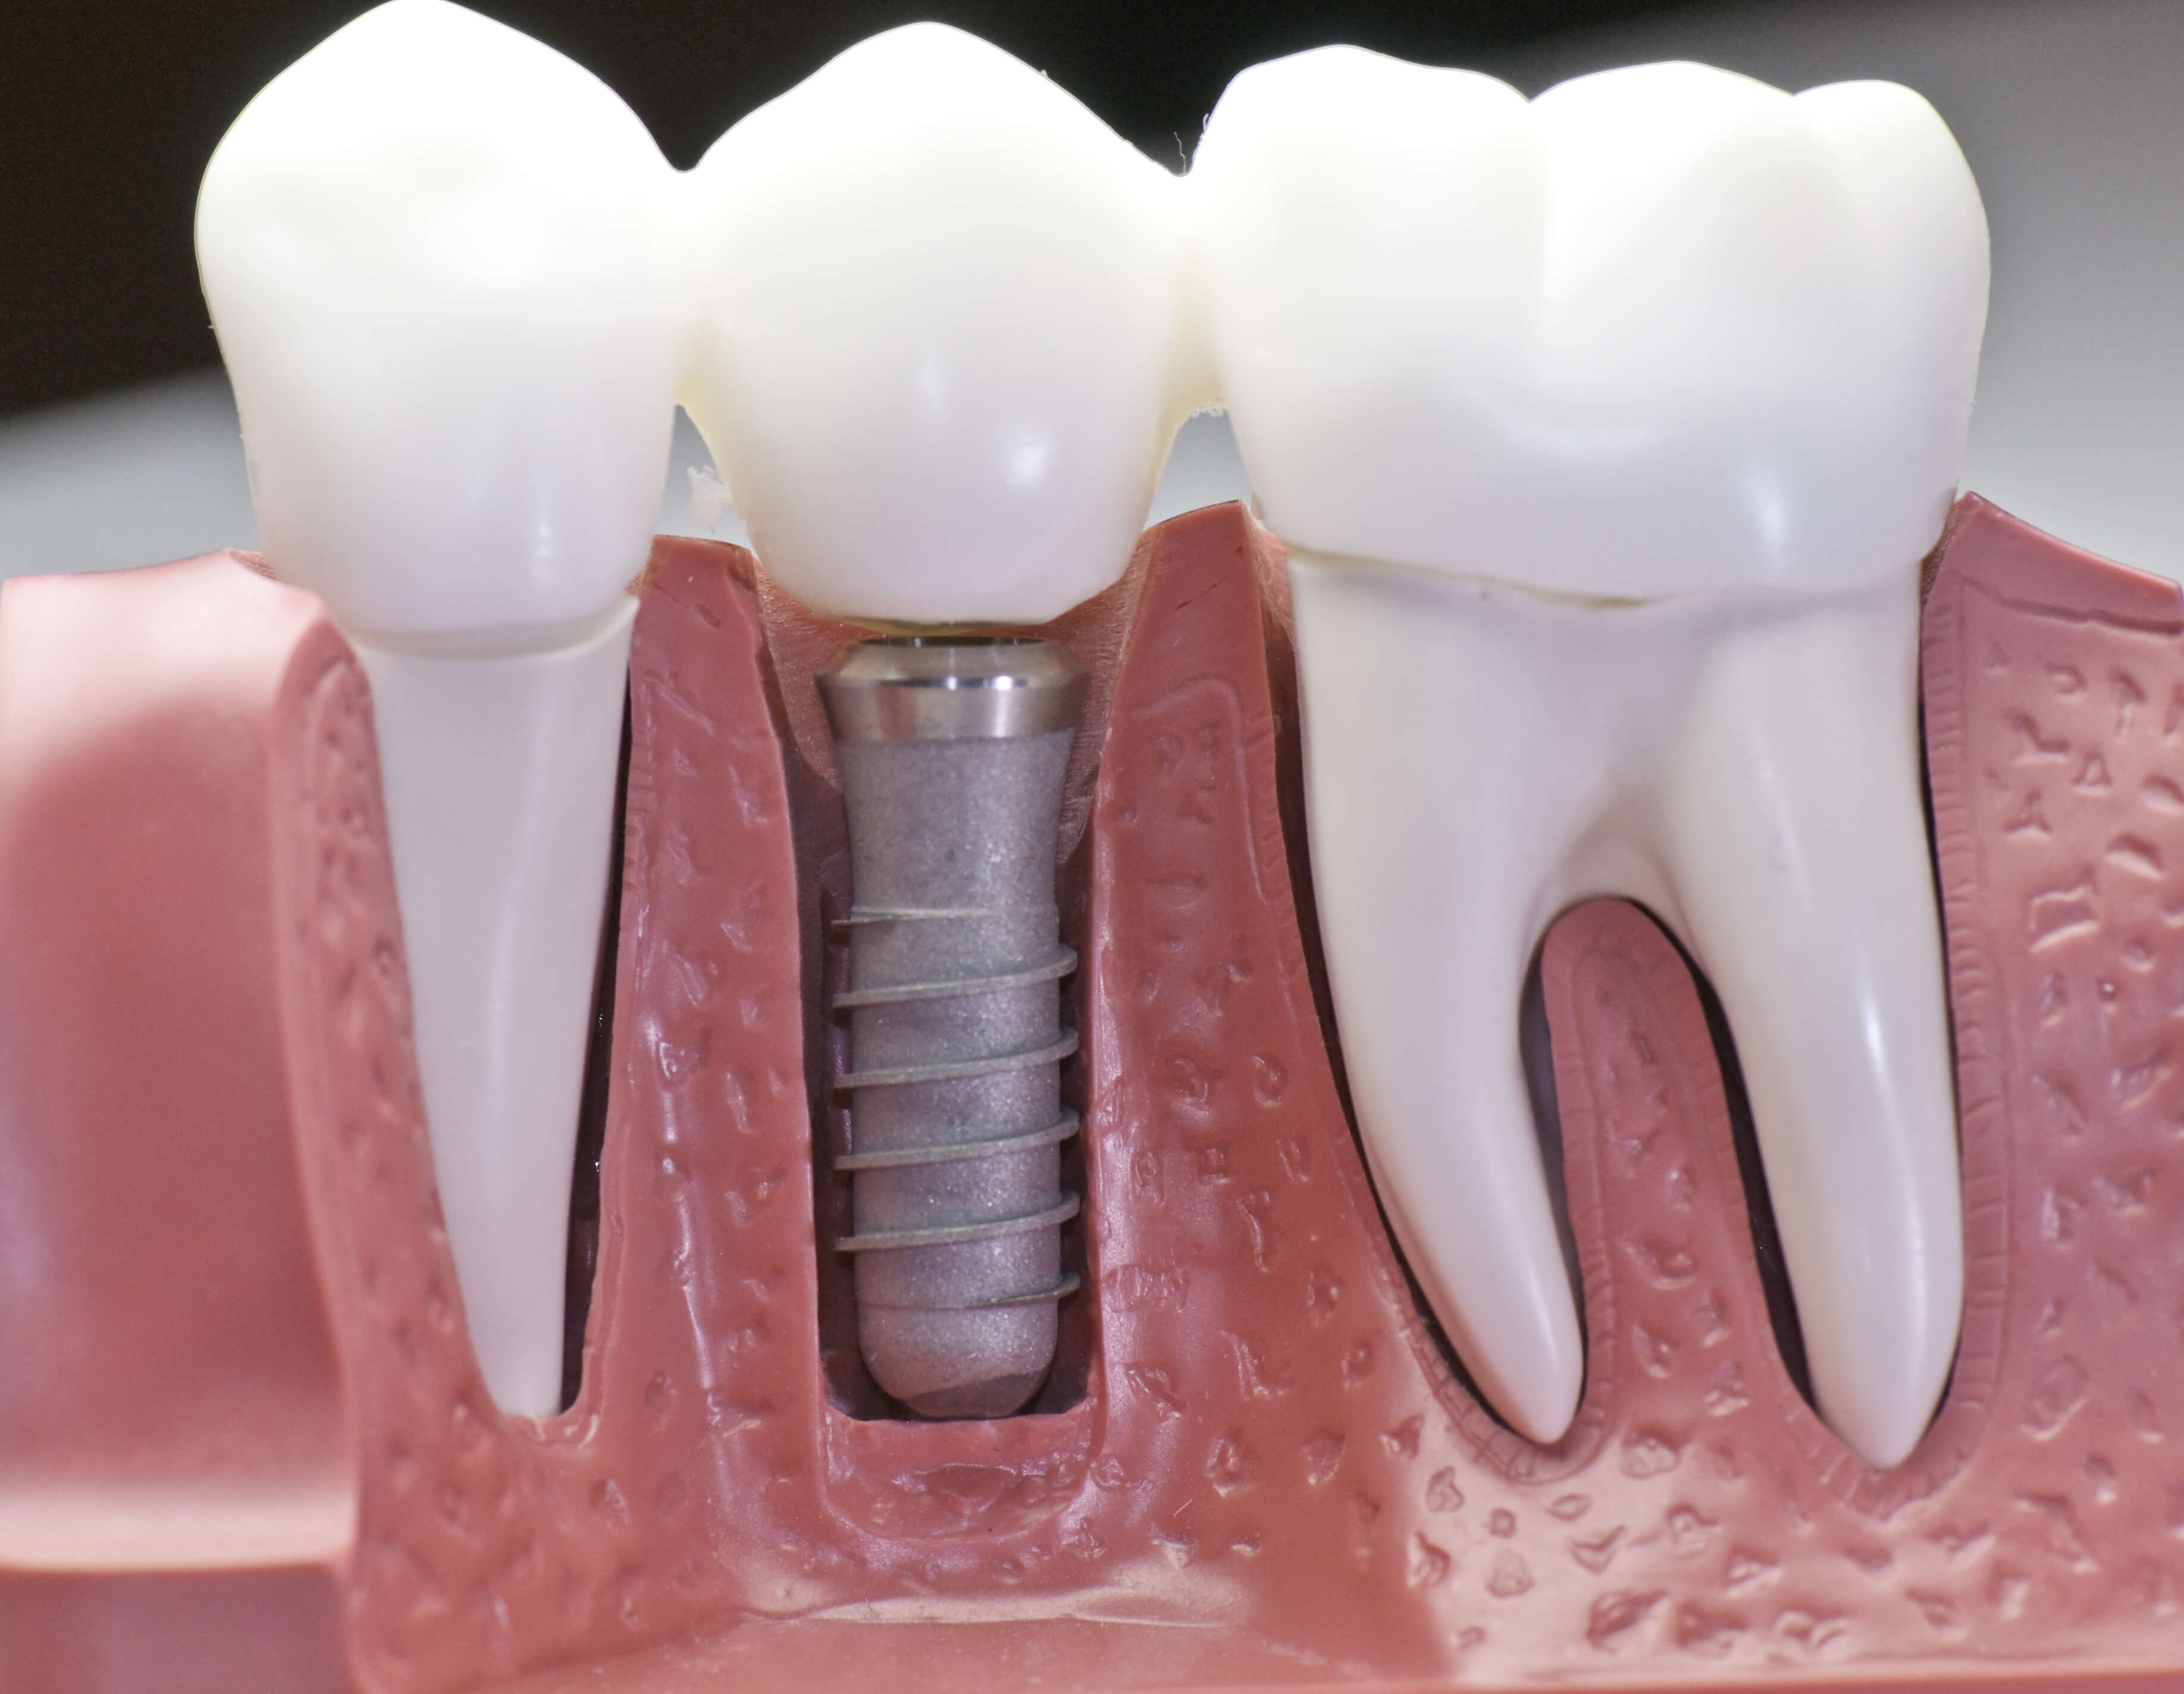

Just like dental crowns, bridges are also fixed prosthetic devices

that bridge the gap created by one or more missing teeth. A typical

bridge is composed of one or more artificial teeth which are called

pontics, held in place by two dental crowns or abutments. They are

cemented onto the supporting teeth, or in some cases, fixed on an

implant that has been placed next to the missing teeth.